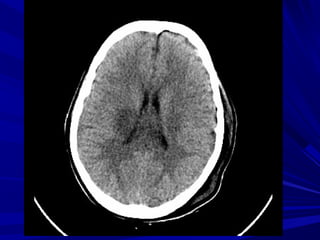

GIAÛI PHAÃU TREÂN CAÙC LÔÙP CAÉTGIAÛI PHAÃU TREÂN CAÙC LÔÙP CAÉT

DUØNG HEÄ THOÁNG NAÕO THAÁTDUØNG HEÄ THOÁNG NAÕO THAÁT

LAØM MOÁC:LAØM MOÁC:

 Naõo thaát beân.Naõo thaát beân.

 Naõo thaát III.Naõo thaát III.

 Naõo thaát IV.Naõo thaát IV.

 Dòch naõo tuûy & caùc beåDòch naõo tuûy & caùc beå

naõonaõo